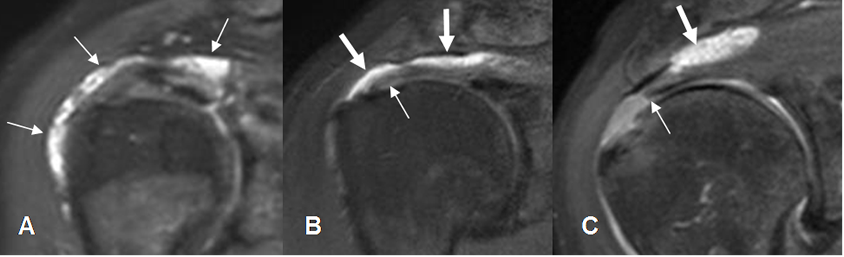

Fig

112. Líquido en la bursa SASD.

A: RM coronal en STIR. Presencia de líquido con sinovitis asociada, por bursitis.

B: RM coronal en STIR. Tendinitis del supraespinoso (Flecha delgada), con líquido en la bursa SASD. (Flechas gruesas).

C: RM coronal en STIR. Ruptura retraída del supraespinoso (Flecha delgada), con líquido a nivel subacromial. (Flecha gruesa).